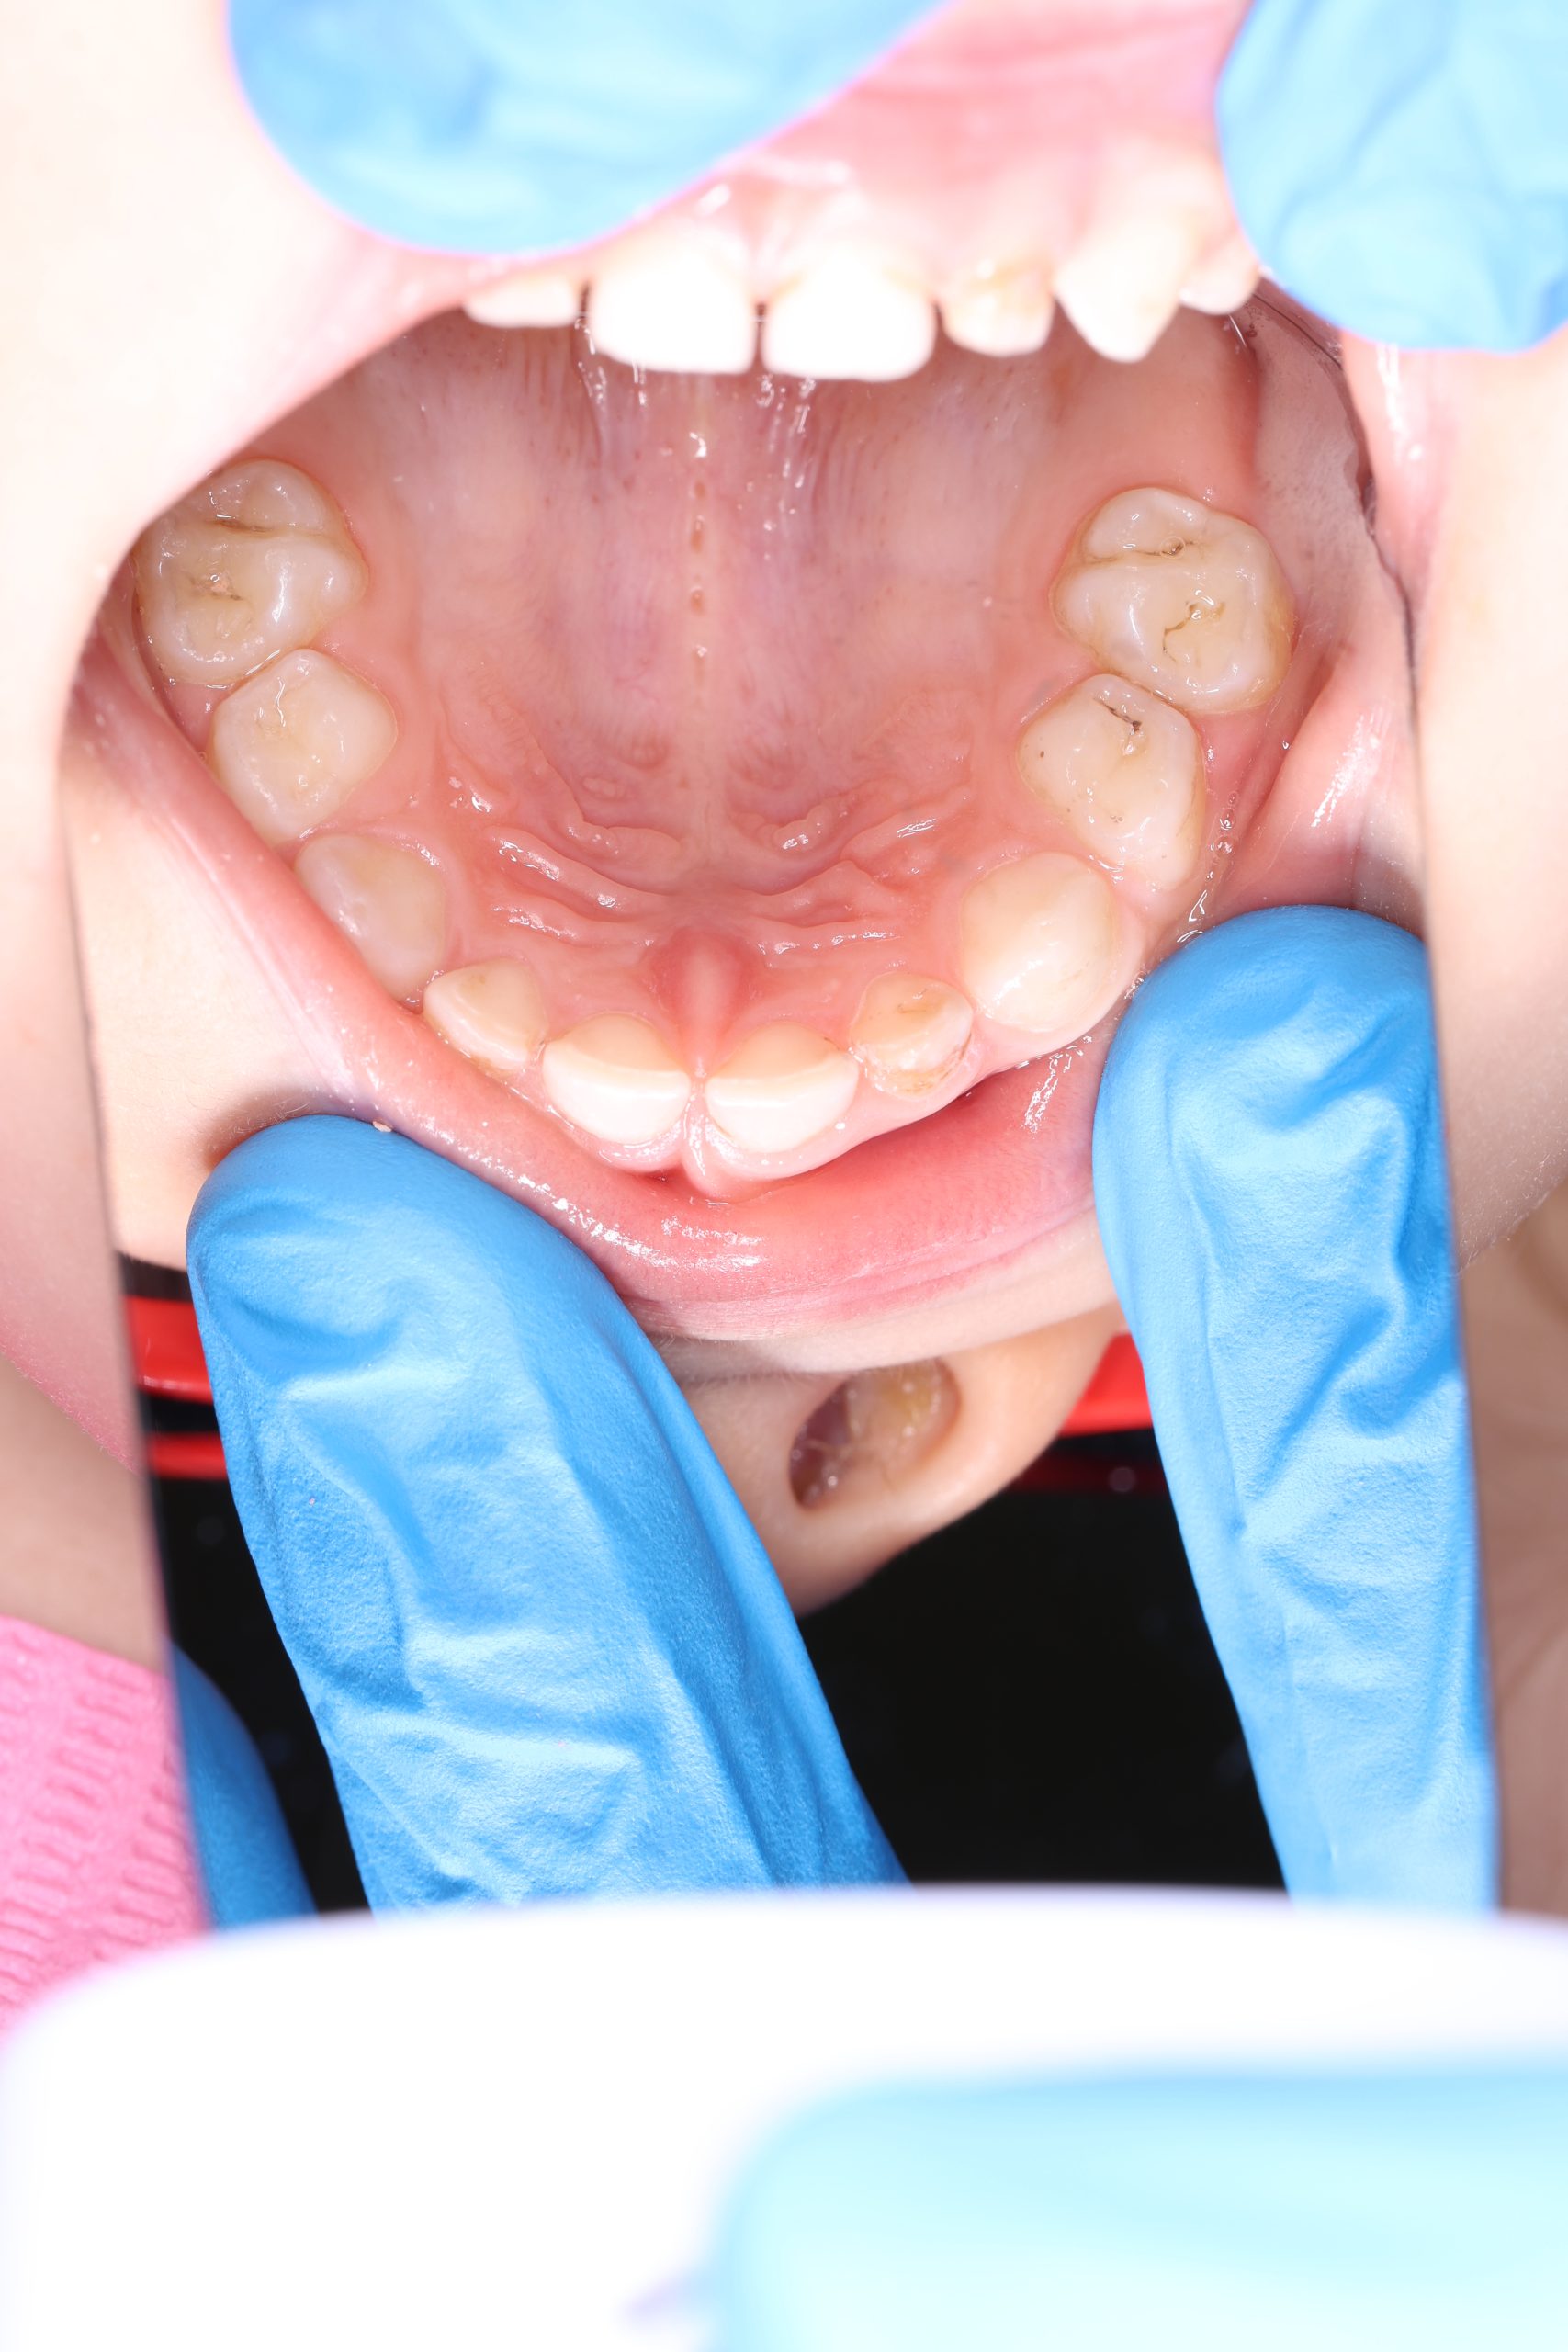

We examine the condition of teeth, gums, and bite. - Plaque Disclosure with Special Indicators

Areas that weren’t cleaned well appear purple. The darker the shade, the older the plaque. This helps both kids and parents understand where brushing needs to improve. - Brushing Training & Home Care Tools Selection